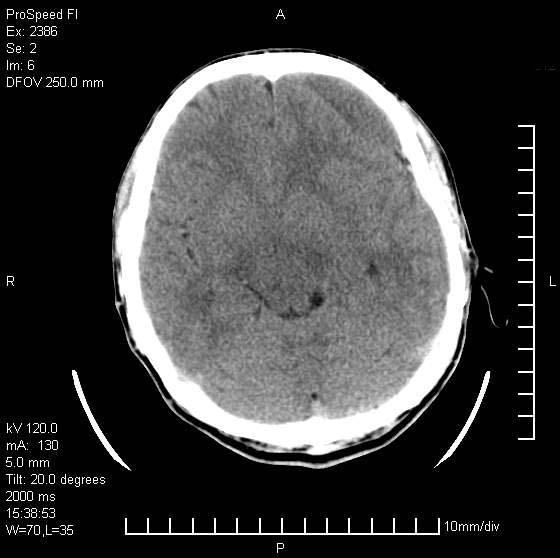

以下是引用天南地北在2007-9-19 18:43:00的发言:[br]典型慢性硬膜外血肿[br][br][本贴已被 天南地北 于 2007-9-19 18:44:11 修改过]

以下是引用曼一拍在2007-9-20 11:06:00的发言:[br]支持慢性硬膜下血肿.[br]慢性硬膜下积液:血肿有包膜,ct值稍高于脑脊液,增强可有染色。不典型者血肿可多呈梭形.是硬脑膜与蛛网膜之间的潜在腔隙内的血肿。[br]鉴别:[br]1\\硬膜外血肿:是颅脑外伤后脑膜或板障内血管破裂,血液在颅骨与硬膜之间积聚所致.通常是脑膜动脉破裂,也可因静脉窦破裂或颅骨的板障静脉出血,发生于外伤的着力部,常与颅骨骨折并存。脑膜动脉出血则急,若是板障静脉出血在则可有慢性。[br]2\\硬膜下积液:(硬膜下水瘤)[br]是由于蛛网膜破裂,脑脊液经蛛网膜破口进入硬膜下腔不能回流。或水肿阻塞而形成。[br]ct表现:颅骨内板下方新月形低密度区近似脑脊液密度;占位效应清,周围无脑水肿。[br]